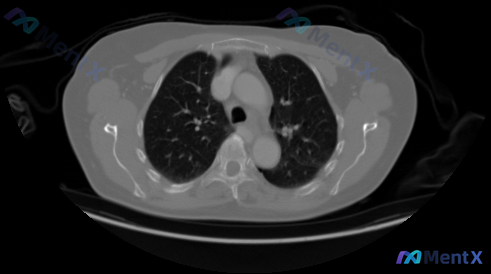

这是一张胸部CT肺窗横断面图像(双肺上野层面):

- 肺实质与气道:肺纹理清晰走行自然,未见实性结节、磨玻璃结节或肿块影,未见异常浸润影、间质改变;各级支气管管腔通畅,管壁无增厚,无支气管扩张或粘液嵌塞;两肺透亮度正常,无肺气肿、肺大疱。

- 纵隔与胸膜腔:纵隔居中,主动脉弓及气管轮廓清晰,未见纵隔肿块;纵隔内无明显肿大淋巴结;双侧胸膜光滑,无增厚、积液或气胸;所示肋骨、胸椎、肩胛骨骨质结构完整,无骨质破坏或增生。

- 整体:双侧肺野高度对称,单张静态图像未见急慢性病理改变。